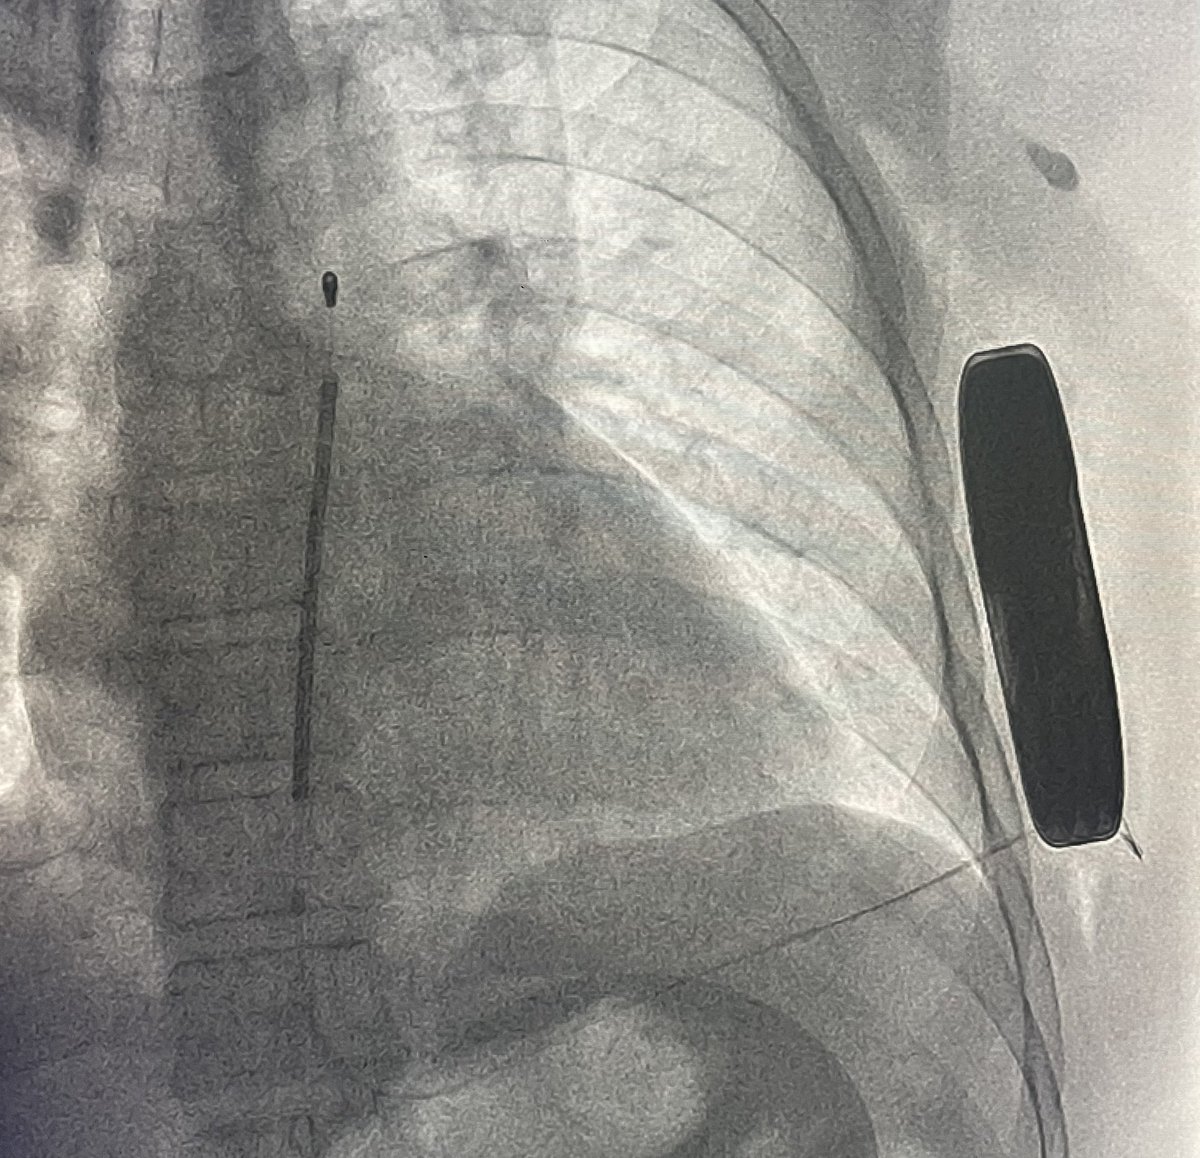

Bye bye anesthesiologists!…first S-ICD implanted only with local anesthesia in Chile!!!…at Hospital last Higueras Talcahuano…many thanks to @JorgeERomeroMD for his instrumental manuscript. @FellowEP @hhuang123 @DrRoderickTung @andresenriqueza @Yurgeny @BostonSciLatam

3

13